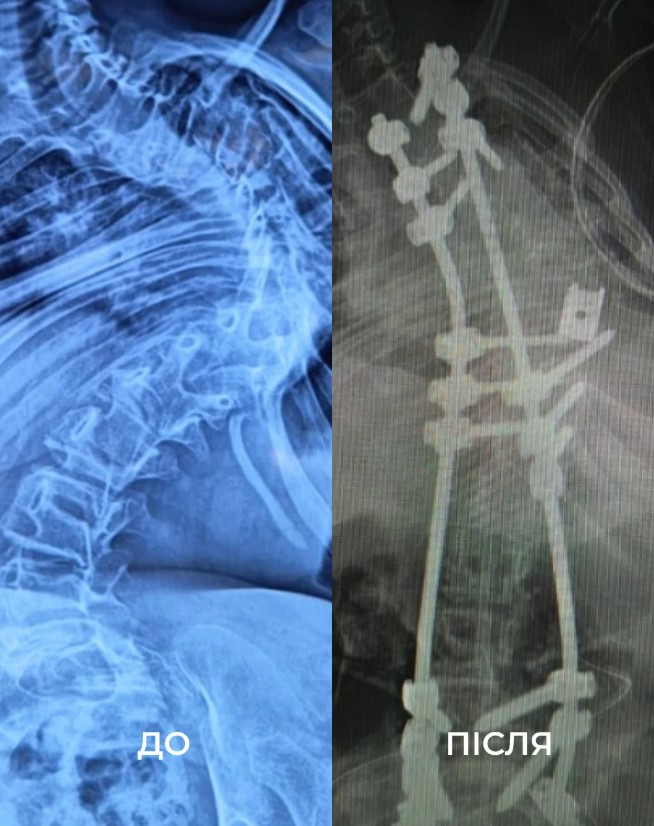

18 часов под наркозом. Во Львове хирурги выровняли позвоночник подростка, который был изогнут полумесяцем

Во Львове хирурги Детской больницы святого Николая прооперировали 12-летнюю Викторию с миопатией Бетлема – редким заболеванием, которое характеризуется врожденно слабыми мышцами и приводит к тяжелому сколиозу. Об этом 26 августа сообщило Первое медицинское объединение города.

Семья – из Сходницы. По словам матери пациентки, она заметила, что позвоночник ребенка изгибается полумесяцем, когда ему было еще шесть месяцев, и с годами состояние только ухудшалось. Женщина рассказала, что Виктория ощущала постоянную боль, одышку и не могла долго сидеть. Позвоночник ребенка искривился на 160°, в результате чего она передвигалась при помощи двух ходунков, а в школе – на колесном кресле. Часто бывала в больницах и на реабилитации.

"Чтобы исправить ее сколиоз, нам нужно было удалить целый позвонок. В первый день операции мы закрепили ее позвоночник винтами. А потом уже на второй день удалили несколько ребер, изолировали спинной мозг и установили титановую клетку для поддержки позвоночника. А потом медленно выпрямляли его вместе с моей коллегой, нейрофизиологом Меган Маллани", – рассказал американский ортопед-травматолог Марк Диржка.

Виктория провела под наркозом 18 часов, а из-за слишком слабых мышц две следующие недели пробыла в реанимации под кислородом. В конце концов хирургам удалось выровнять позвоночник девочки на 85%, отметили в медобъединении и выразили надежду, что подросток сможет когда-нибудь побегать вместе со сверстниками.